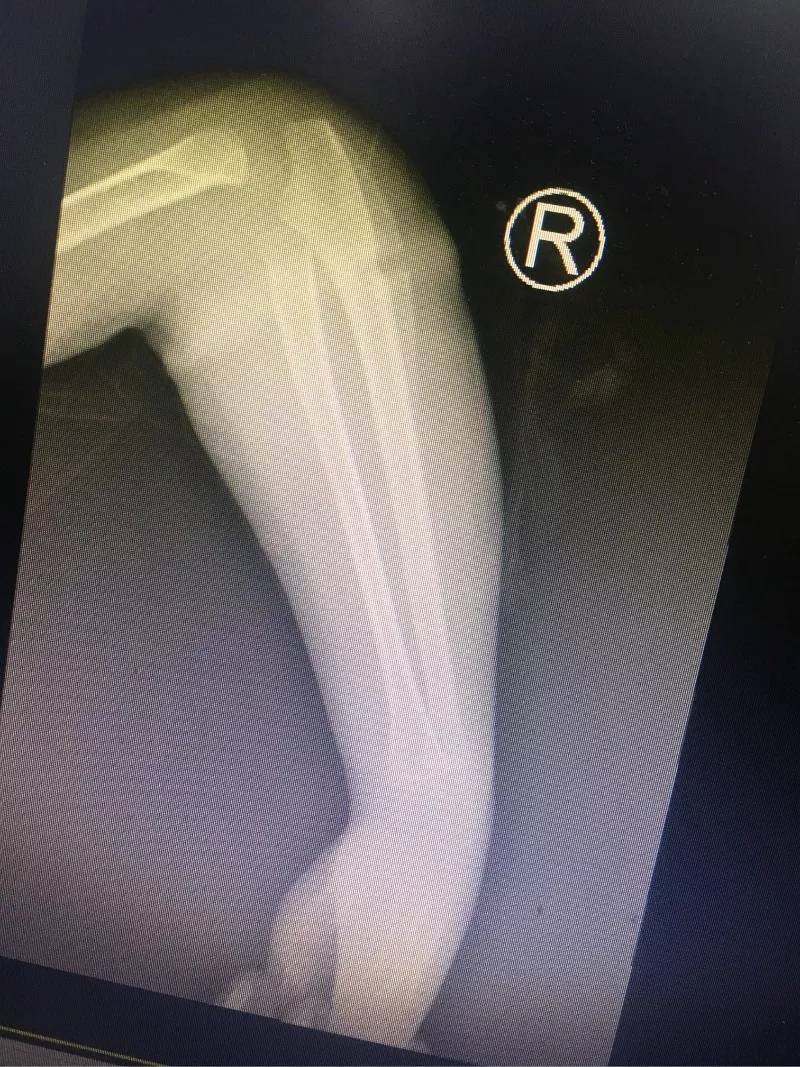

4歲的樂樂長期跟着爺爺奶奶生活,不知從什麼時候開始,**右側手臂莫名其妙長了一圈“圓環”。**最初家裏人沒有在意這個“圓環”,哪知道樂樂的右前臂一天比一天更紅腫。2018年過年後,樂樂手臂嚴重腫脹,疼痛,而且手指活動受限。看到孩子右前臂比左前臂足足腫大了一圈,這時樂樂的家人才擔心起來。

葉主任看了樂樂的手臂,告訴孩子的家長,“圓環”很可能是橡皮筋導致的。雖然樂樂父母不大相信,還是聽從葉主任的建議,讓樂樂入院了。沒多久,入院後B超檢查結果出來了,也證實了葉主任的診斷是正確的。

有了明確的診斷,骨科各位醫生開始為樂樂手術。這個手術並不難,無影燈下,歷經半小時就將“圓環”擒拿歸案,把長在肉裏的環形橡皮筋取了出來,徹底解決了樂樂的病痛。